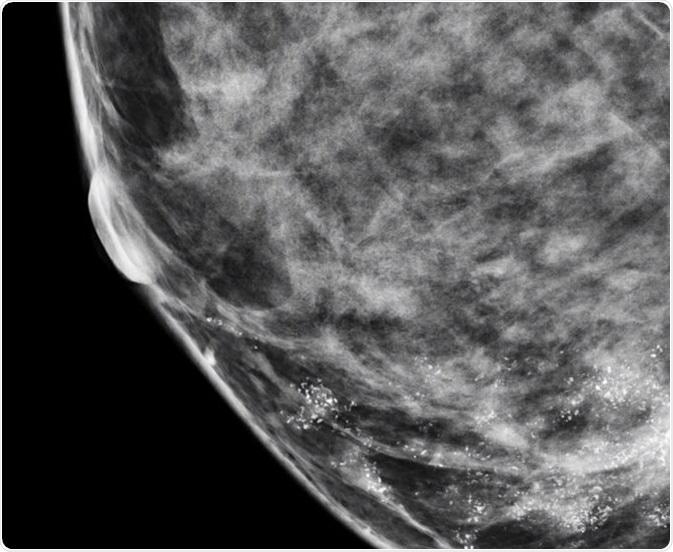

Microcalcifications are actually calcium deposits and are seen as tiny, white dots on a mammogram. They are much less common and are mostly a result of mutations in the breast tissue, though they can be caused by other factors. The appearance of microcalcifications is widely used in the detection of breast cancer at an early stage and can lead to better outcomes.

Nearly 50% of non-palpable cancers in the breast are detected only by the presence of microcalcifications on a mammogram, and approximately 93% of people with ductal carcinoma in situ (DCIS) also present with microcalcifications. Microcalcifications in the breast are very common in women and some studies have observed significant variations in the elemental composition of benign and malignant calcifications.

In general, when the distribution of microcalcifications is diffuse or bilateral, when they have a round and/or punctuate shape, or when they are scattered in the breast tissue, the condition is usually benign. On the other hand, if microcalcifications have a linear or branching pattern with irregular borders, or if they have variable density, or when they are distributed in a haphazard or segmental way, there is a high probability that it is ductal carcinoma in situ or malignant cancer.

Radiologists usually term a variable distribution density where the breast microcalcifications are closely packed at one place and widely spread at another as ‘suspicious’, and not definitive, for cancer. It is referred to as ‘cluster of suspicious-looking microcalcifications0 on a mammogram report.